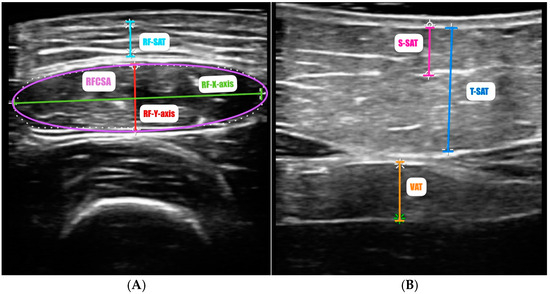

- García-Almeida, J.M.; García-García, C.; Vegas-Aguilar, I.M.; Ballesteros Pomar, M.D.; Cornejo-Pareja, I.M.; Fernández Medina, B.; de Luis Román, D.A.; Bellido Guerrero, D.; Bretón Lesmes, I.; Tinahones Madueño, F.J. Nutritional Ultrasound®: Conceptualisation, Technical Considerations and Standardisation. Endocrinol. Diabetes Nutr. 2023, 70, 74–84. [Google Scholar] [CrossRef]

| Nutritional ultrasound®: rectus femoris muscle | |||

| RFCSA (cm2) | 2.8 ± 1.0 | 2.9 ± 1.02 | 2.2 ± 0.8 |

| RF-Y-axis (cm) | 0.8 ± 0.3 | 0.87 ± 0.27 | 0.77 ± 0.22 |

| RF-X-axis | 3.65 ± 0.50 | 3.76 ± 0.44 | 3.31 ± 0.55 |

| RF-AT (cm) | 0.41 (0.23–0.74) | 0.35 (0.24–0.55) | 0.78 (0.22–1.42) |

| Nutritional ultrasound®: abdominal adipose tissue | |||

| T-SAT (cm) | 1.4 (0.5–1.9) | 1.35 (0.47–1.85) | 1.41 (0.82–2.43) |

| S-SAT (cm) | 0.52 (0.28–0.87) | 0.47 (0.26–0.79) | 0.68 (0.35–1.06) |

| VAT (cm) | 0.55 (0.31–0.73) | 0.52 (0.30–0.65) | 0.58 (0.33–0.95) |